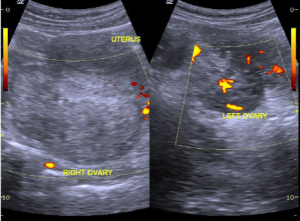

Ovarian torsion on ultrasound with enlarged ovary and absent vascular flow.